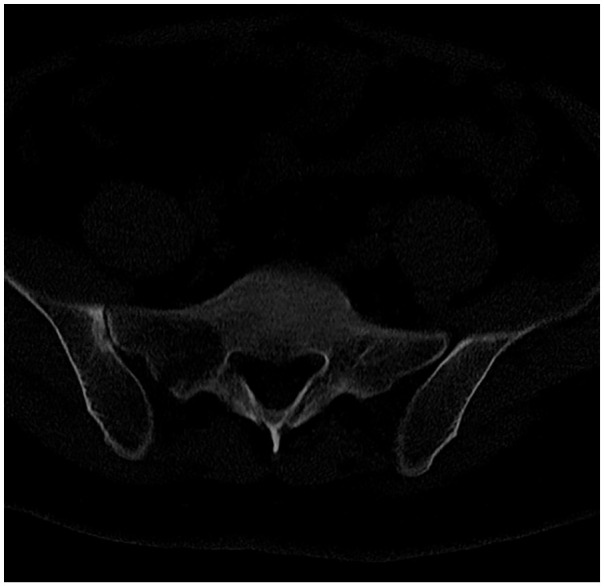

Abstract Image